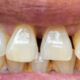

Odbudowa zęba na włóknie szklanym – zalety i przeciwwskazania

Odbudowa zęba na włóknie szklanym to popularny sposób zakończenia leczenia endodontycznego (kanałowego). Zabieg…